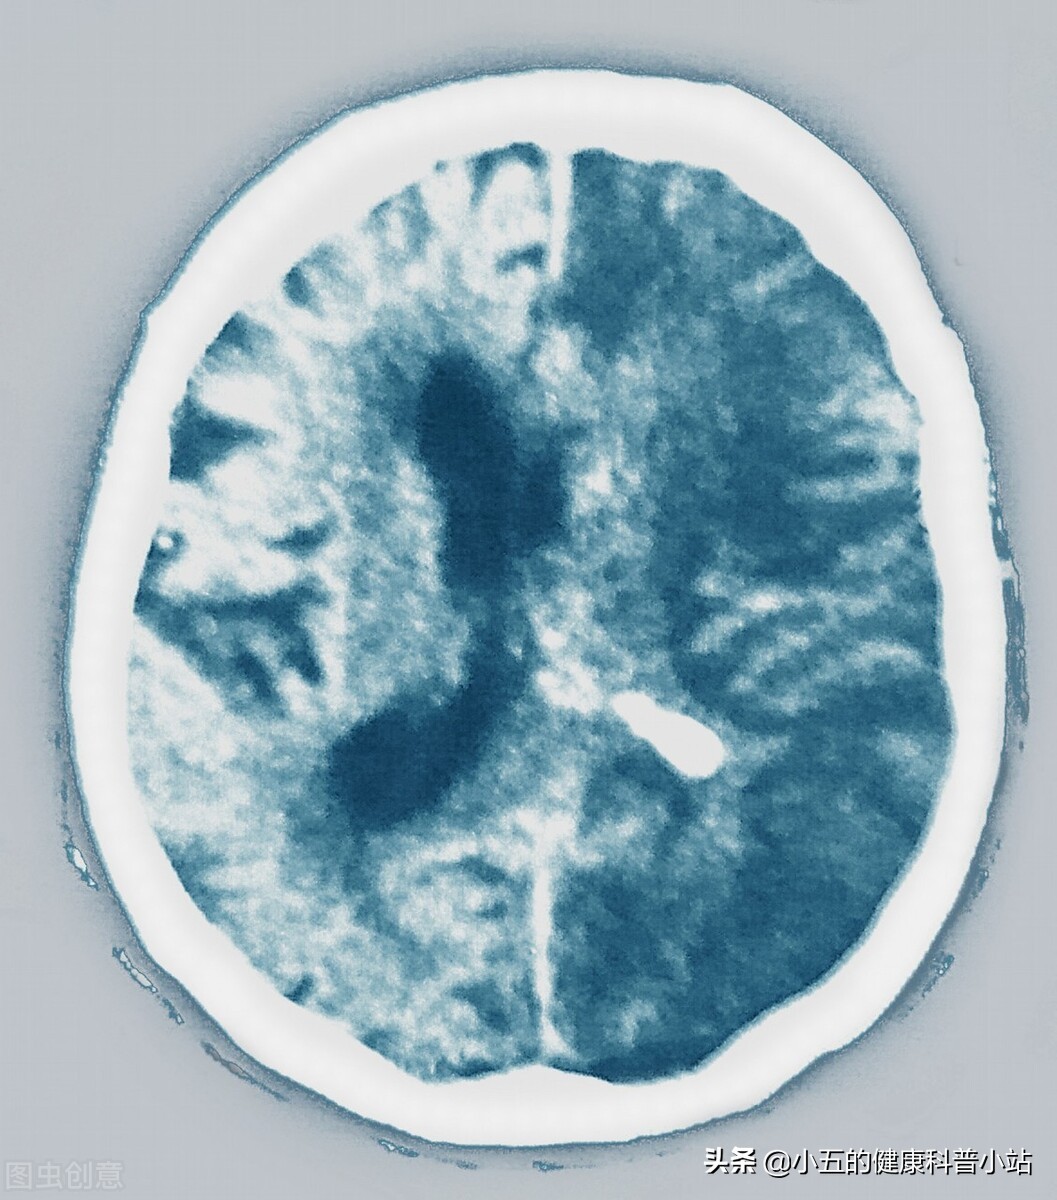

脑卒中

房颤时心房丧失收缩功能,血液容易在心房内淤滞而形成血栓,血栓脱落后可随着血液流至全身各处。根据统计房颤患者出现脑卒中的几率是没有房颤患者的15-20倍 ,2003年底我国发表了中华医学会组织的中国除*藏西**以外大陆内地40家医院近万人1999~2001年房颤的回顾性研究结果表明房颤患者中脑卒中的发病率为17.5%,其中42.3%恢复功能‚49.7%中、重度致残‚8.0%死亡。其次,房颤的患者还容易诱发肢体动脉栓塞,也就是血栓进入肢体动脉中造成动脉栓塞,肢体动脉栓塞的患者会出现突发性的剧烈疼痛,伴有肢体快速肿胀,严重时甚至发生肢体缺血性坏死,要截肢才能彻底治疗。